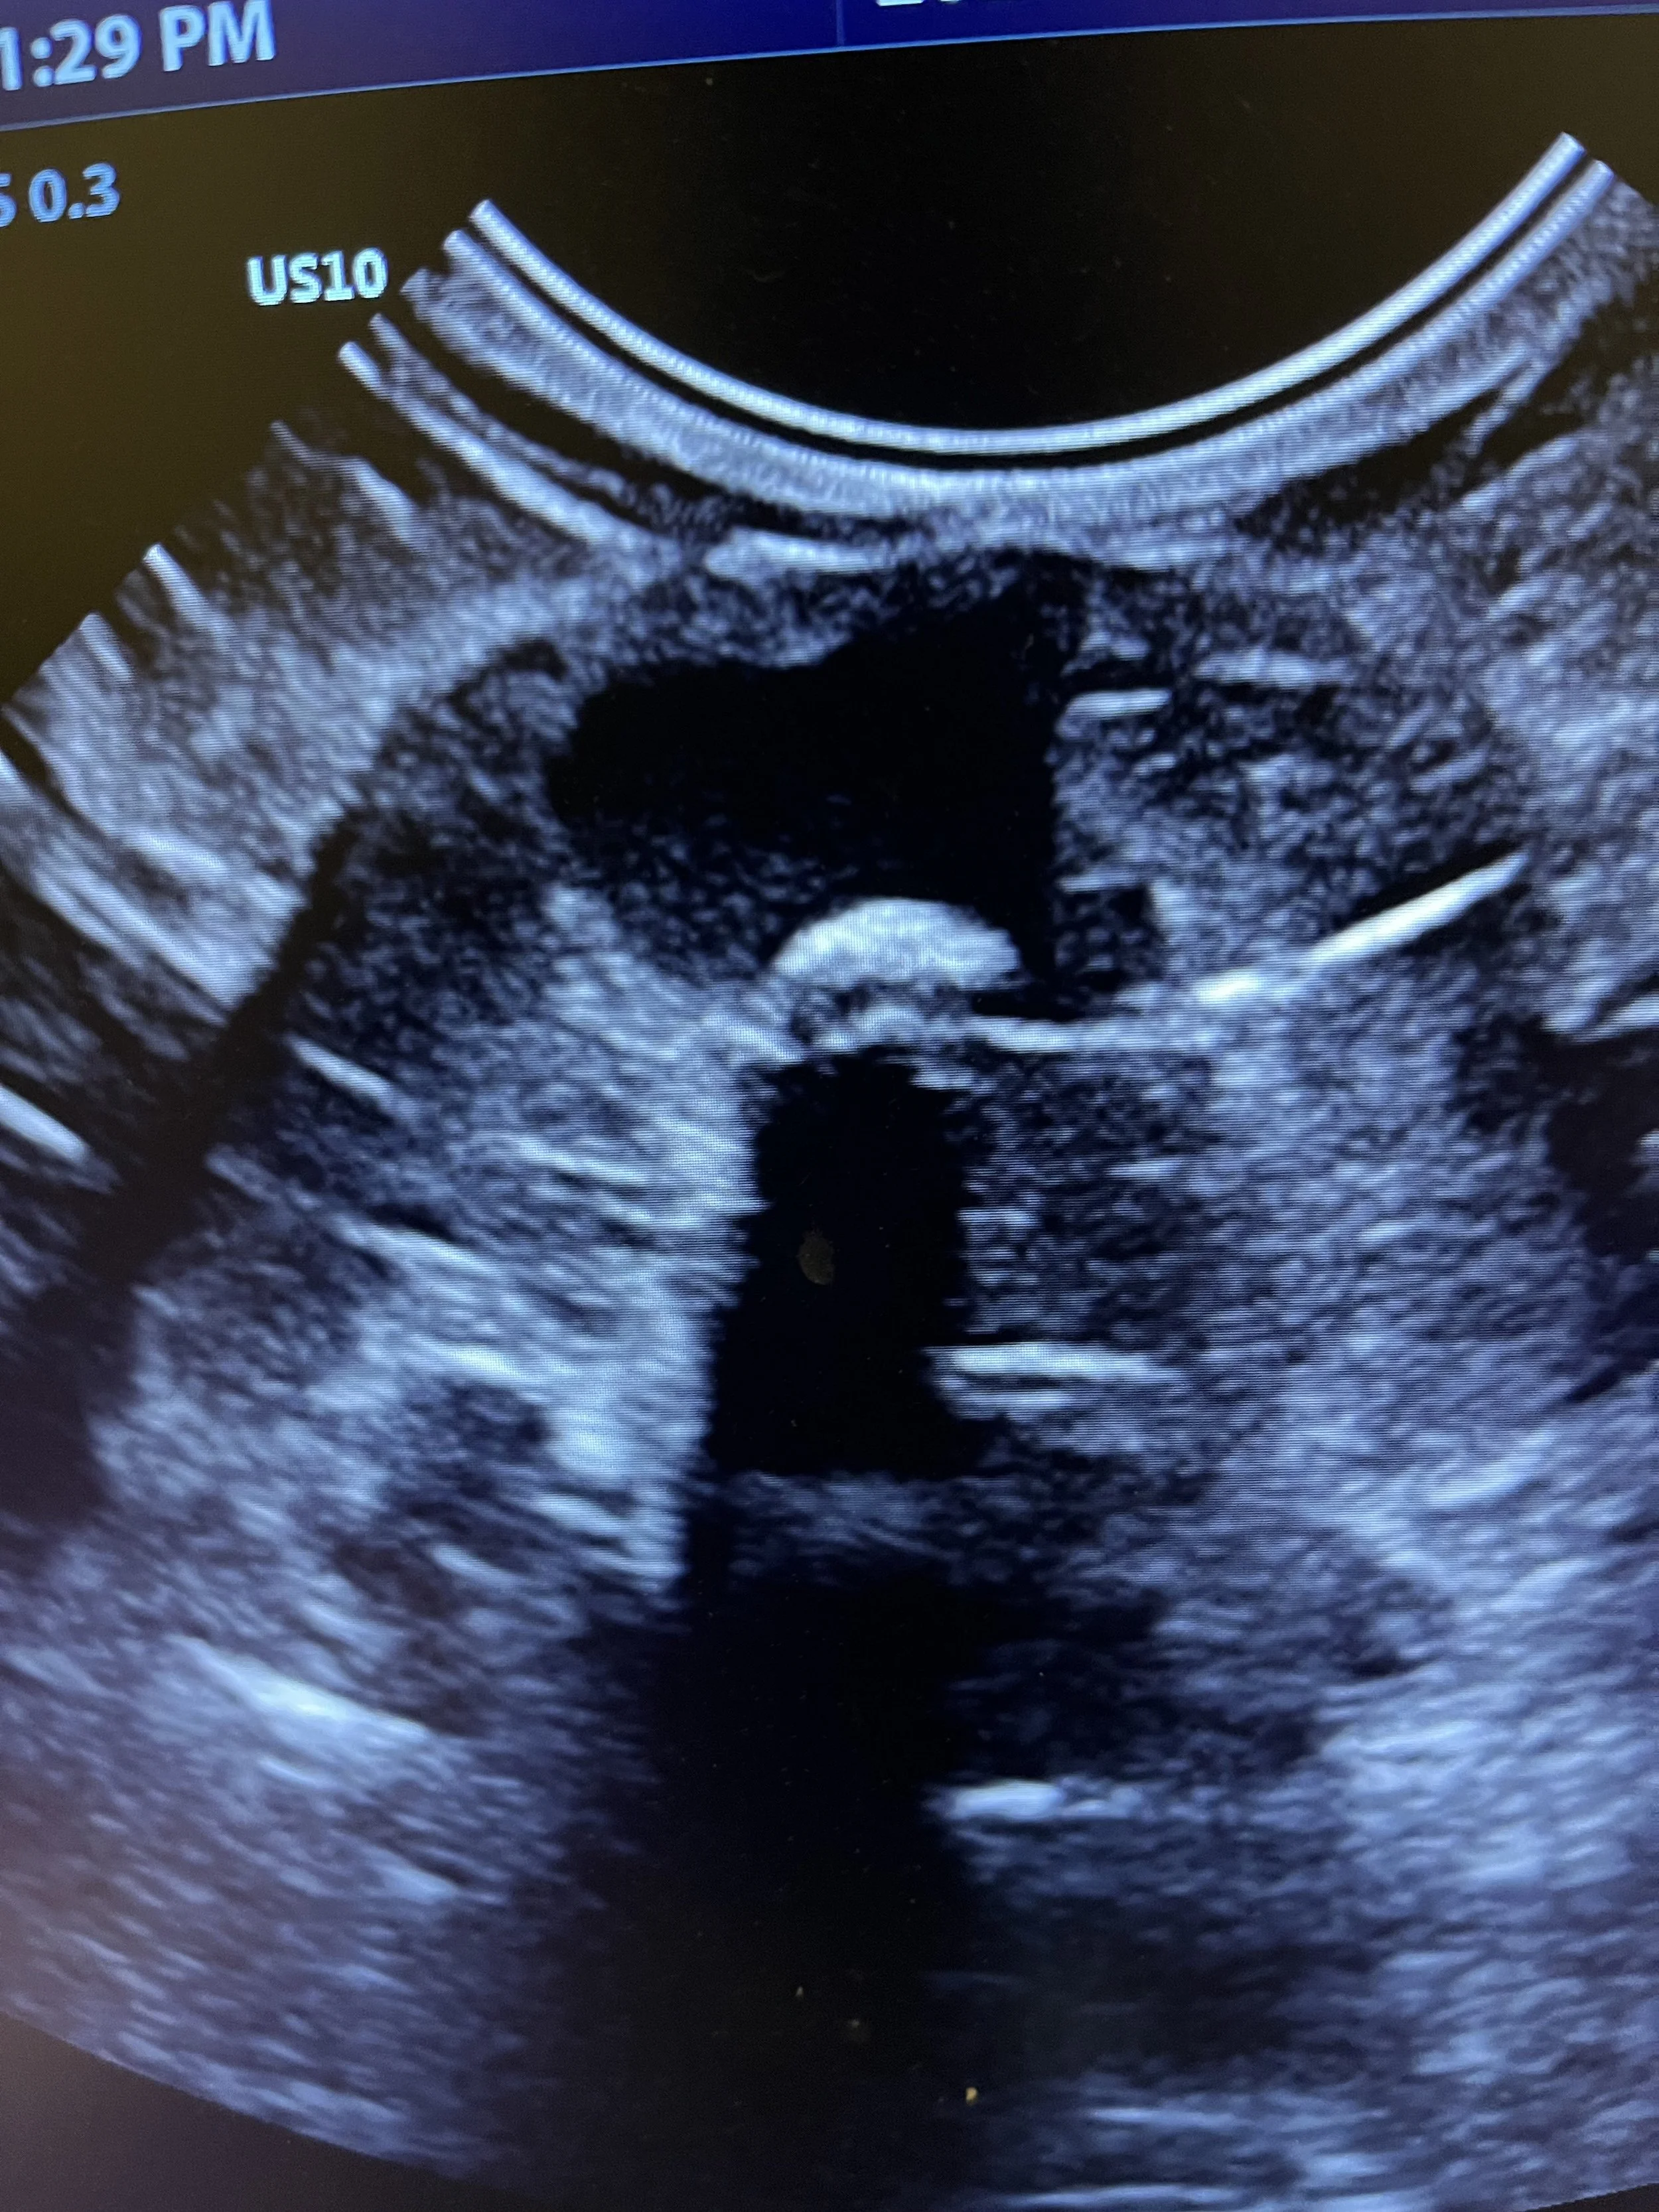

At some point in their life, your dog or cat will need more than preventive health care. Kingdom’s medical team is here to help, with advanced diagnostic and medical care. We will give you confident assurance that with our highly trained medical staff, your pet is in the very best hands possible. We perform diagnostics including bloodwork, radiographs, and ultrasound during your appointment whenever possible, so you can get the answers you need for your sick pet and start the appropriate treatment plan right away.